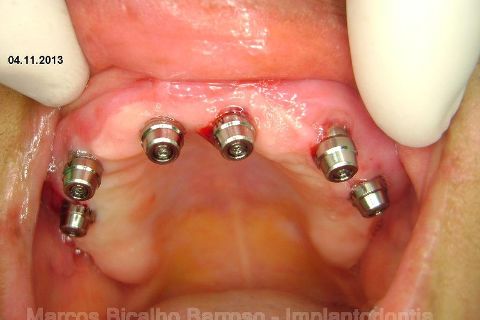

FASE PROTÉTICA DA REABILITAÇÃO EM MAXILA ATRÓFICA...incluindo a reabertura, instalação dos minipilares e PTR provisória reembasada sobre os cilindros de proteção.